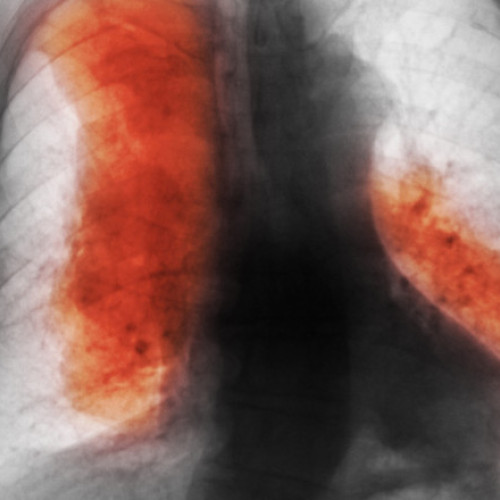

Principalul factor al acestei creșteri este îmbătrânirea populației și majorarea populației globale, în special în țările cu venituri mici și medii, unde se înregistrează cele mai multe cazuri noi. Studiul menționează că în prezent cancerul mamar este cel mai frecvent diagnosticat, în timp ce cel pulmonar rămâne principala cauză de deces.